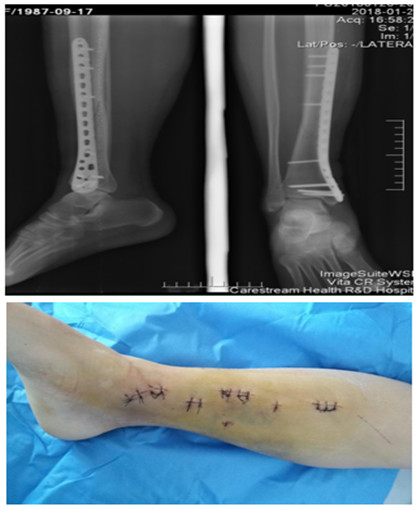

随着时代的发展,医疗技术的不断更新,微创、个性化是未来骨科的发展方向。创伤骨科采用MIPPO技术治疗四肢骨折具有创伤小、术中术后出血少、伤口美观、固定牢固、骨折愈合率高以及能够早期功能锻炼的优点。延安大学咸阳医院骨科二病区紧跟国际骨科前沿,结合国内及地区现状积极开展微创手术,效果满意。

我院首例胫骨骨折MIPPO技术